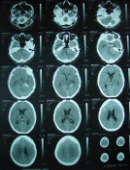

CT-scan done showing complete resection of the tumor with part of the hyperostosis left in place at the anterior third of the left pyramid.

Preoperative CT-scan showing the mass with hyperostosis of the left petrous anterior third and calcified tentorium with preoperative MRI  T1 W with contrast showing the tentorial edge meningioma. Immediate postoperative CT-scan demonstrating practical radical resection of the tumor